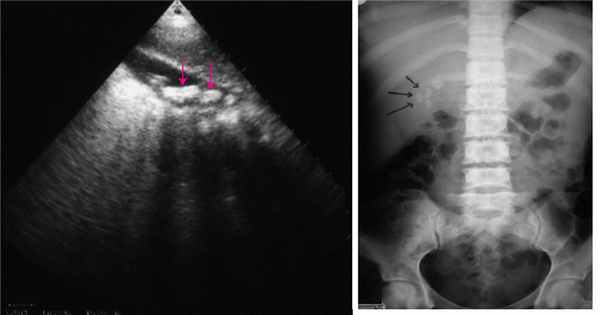

УЗИ органов брюшной полости и почек.

Печень: косой внутренний размер правой доли 189 мм краниокаудальный размер левой доли 90 мм, контуры ровные, высокая эхогенность, нечеткость сосудистого рисунка, структура неоднородная, воротная вена 10 мм в диаметре, желчные ходы не расширены, холедох диаметром 6 мм. Желчный пузырь 73*26 мм, толщина стенок 2 мм. Единичные конкременты до 7 мм. Поджелудочная железа головка 39 мм, тело 16 мм, хвост 18 мм, структура неоднородная, контуры ровные. Селезенка 89x48 мм, однородной структуры. Почки: размеры - правая 98*41 мм, левая 102*51 мм, расположение обычное. Паренхима сохранена справа 12 мм, слева 16 мм, конкременты не выявлены, полостная система не расширена, не деформирована.

Заключение: увеличение печени за счет правой доли. УЗИ-признаки жирового гепатоза. Диффузные изменения структуры поджелудочной железы. ЖКБ. Мелкие единичные конкременты желчного пузыря.

- УЗИ органов брюшной полости. Ультразвуковое исследование визуализирует инфаркт в печеночной ткани как очаг низкой эхогенности, который имеет треугольную или неправильную форму. Ишемизированный участок располагается в периферической зоне органа, резко отграничен от интактной паренхимы. Для оценки печеночного кровотока используют допплерографию.